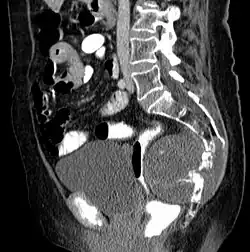

Chordome sind langsam und destruktiv wachsende Tumoren der Wirbelsäule und der Schädelbasis, die in etwa 10 % der Fälle metastasieren.

Chordome werden manchmal zu den Knochentumoren gezählt, obwohl sie nicht aus Knochengewebe stammen, sondern aus Resten der Chorda dorsalis (Notochordoa) an den Enden der Wirbelsäule. Damit lassen sich auch ihre Hauptlokalisationen, nämlich Schädelbasis und Steißbein, erklären. Die ICD-O-3 klassifiziert sie unter die Sonstigen Tumoren des Nervensystems (Nr. 937).